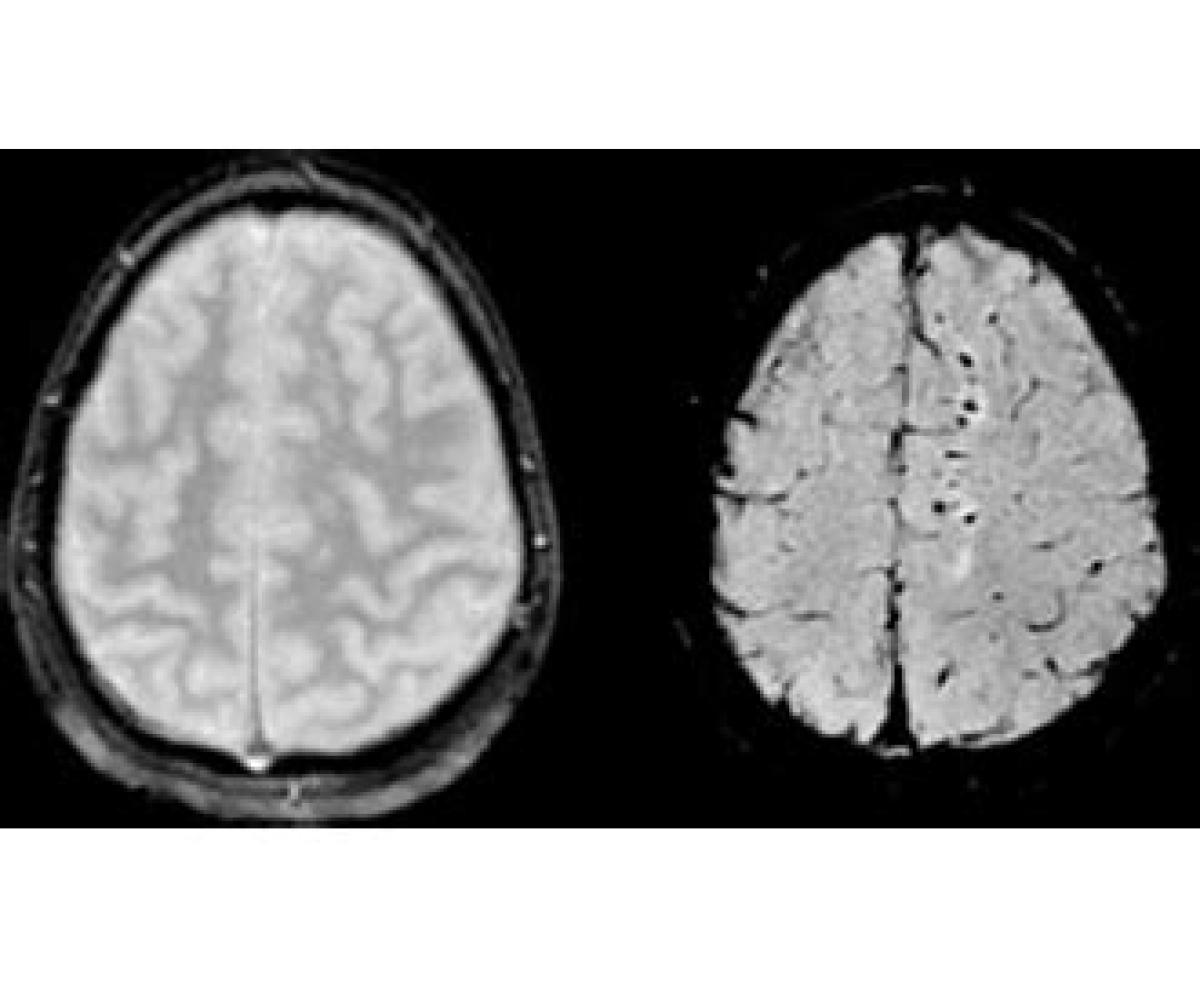

آسیب منتشر آکسونی(diffuse axonal injury): به علت تکان شدید و یا چرخش شدید سر ایجاد میشود. هنگامی که سر بطور ناگهانی تکان میخورد (بصورت شلاقی)بدون اینکه به شیئی برخورد کند، افزایش و کاهش ناگهانی سرعت میتواند به مغز آسیب برساند. پارگی بافت اعصاب در پی این آسیب میتواند کارکرد طبیعی مغز را مختل کرده و به آسیب کلی مغز،کما و حتی مرگ منجر گردد.